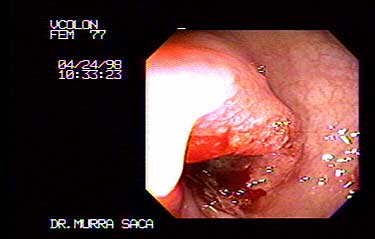

Femenino 77 años con Adenocarcinoma de la unión Recto sigmoides